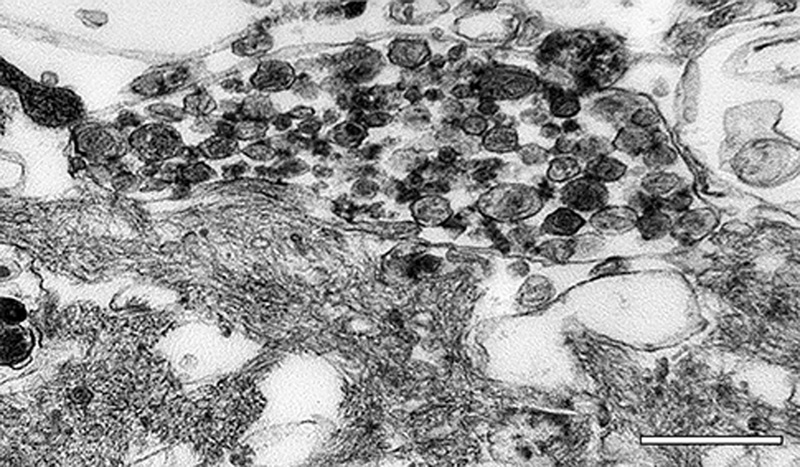

Activated microglia are intimately associated with the fibrillar Aβ in classical Aβ plaques [139, 327-330] (Figure 20). They occupy much of the space between the plaque core and outer corona, and their processes interdigitate with the bundles of amyloid [311, 327]. The discovery that loss of function mutations in TREM2 are a strong risk factor for AD has heightened interest in the role of microglia in neurodegeneration [299, 306]. TREM2 is a cell-surface immune receptor on many myeloid cells, including microglia, which exclusively express TREM2 in the brain [306]. The production of TREM2 is increased in AD [331], and it mediates the activation and responsiveness of microglia to Aβ-amyloid plaques [332].

Microglia have been thought to either phagocytose [139] or produce [311] multimeric Aβ, and their functional variability makes both actions conceivable, depending on the circumstances.

On the other hand, ultrastructural [311, 340, 341] and experimental [342] investigations have suggested that microglia can generate Aβ-amyloid fibrils. In support of this hypothesis, sustained pharmacologic reduction of microglia significantly diminished Aβ plaque load in a transgenic mouse model [343].

Figure 20. Electron micrographs of a microglial cell in an Aβ-amyloid plaque of an AD patient. The white box in the image on the left denotes the region at higher magnification on the right. The fibrillar bundles of Aβ interdigitate with the microglial soma. Note that the microglial cytoplasm appears artifactually rarefied in this autopsy-derived tissue. Bar = 500 nm (right), 2.8μm (left).